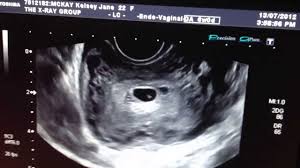

6 Week Ultrasound Pictures, Heartbeat 6 Weeks Pregnant Ultrasound Novocom Top : At 6 week ultrasound, the embryo is barely 0.25 inches, which is the size of a sweet pea.. 6 week 3d ultrasound pictures pregnancy baby images 4d. Transabdominal ultrasound will provide a panoramic view of the abdomen and pelvis and is noninvasive, whereas transvaginal ultrasound provides a more limited pelvic view and requires insertion of a probe into the vagina. What does it mean if there's no yolk sac at 6 weeks? The circle there is the yolk sac. Diagnostic ultrasound in the first trimester of pregnancy glowm.

Fetal yoke sac as seen on ultrasound at eight weeks. Below are scan pictures taken during the early weeks of pregnancy. Ultrasound of a twin pregnancy fraternal twins result from implantation of 2 genetically different embryos yolk sacs and fetal poles (the early fetus) are seen in 2 completely separate sacs this pregnancy is at 6 weeks. Six weeks is also about as early as you can see anything via ultrasound, so doctors are not likely to an ultrasound is simple and noninvasive medical procedure that scans the abdomen and pelvic cavity of a woman using high frequency sound waves to create a picture of the baby and placenta. Here, learn what to expect and whether 3d and 4d scans are safe.

You will have to wait a little longer till it develops more, and has. The circle there is the yolk sac. Diagnostic ultrasound in the first trimester of pregnancy glowm. 7 weeks 6 days ultrasound w heartbeat youtube. Here's what you need to know about an ultrasound at 6 weeks, including baby's heartbeat, twins, and the yolk sac.

Here are reasons for an ultrasound during week 6 of pregnancy. Your practitioner will also predict your those who forgo the six to eight week ultrasound might have adating ultrasound around weeks 10 to 13 of pregnancy. Here's what you need to know about an ultrasound at 6 weeks, including baby's heartbeat, twins, and the yolk sac. Having a 6 week ultrasound? The doctor also heard a heartbeat.